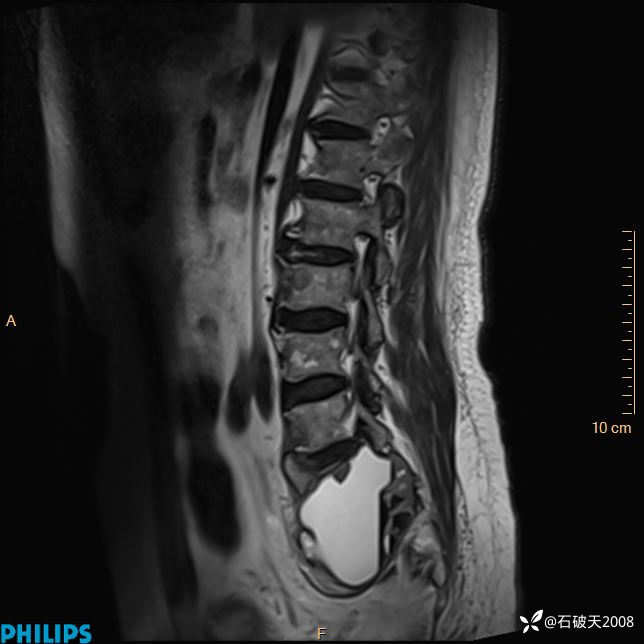

2023年3月份MRI影像

T2矢状位